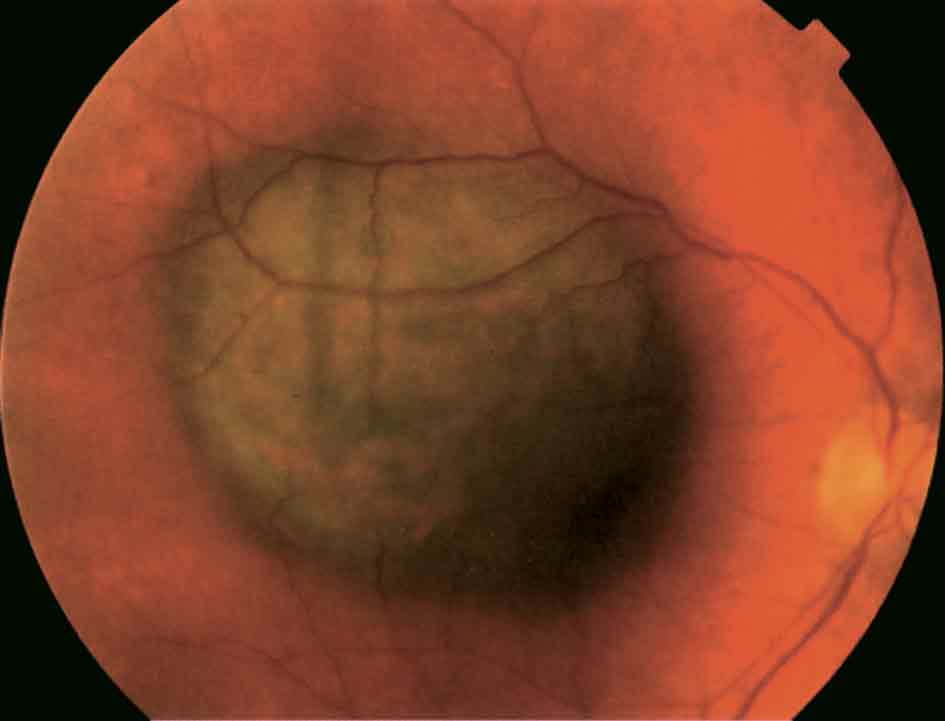

الشكل (6): وحمة مشيمية سليمة.

تصادف الوحمة الميلانينية المشيمية في 5-10% من العرق الأبيض، ونادراً جداً في العرق الأسود، وهي آفة مسطحة أو قليلة الارتفاع مدورة أو بيضوية (الشكل 6). قطر معظم الوحمات أقل من 5 مم وثخنها أقل من ملم واحد، توجد الوحمات غالباً منذ الولادة، ويكبر حجمها على نحو رئيسي في مرحلة قبل البلوغ، ونادراً ما تكبر بعد ذلك. تشخص في معظم الحالات بمنظار قعر العين من دون فحوص خاصة. ومع مرور الزمن قد ترافق هذه الوحمات براريق شفافة drusen (الشكل 7). وتبقى معظم الوحمات من دون أعراض.

أما العلامات التي تتماشى مع تحول الوحمة تحولاً خبيثاً فأهمها: زيادة قطرها وثخنها بالفحوص المكررة وبالتصوير بالأمواج فوق الصوت، وظهور أعراض جديدة كتدني القدرة البصرية وتشوه المرئيات ورؤية شرر ضوئي.